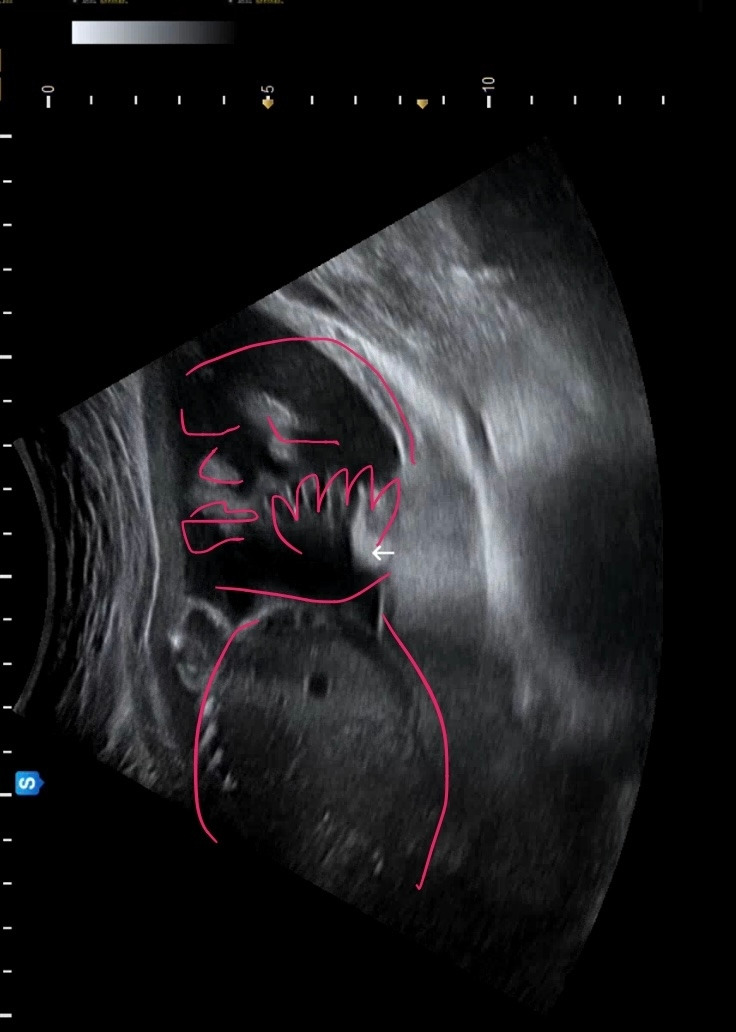

21주차 우리 애기. 손으로 얼굴을 감싼 게 내눈에는 딱 보여서 너무 귀엽다고 남편 보내줬는데 남편은 또 잘 모르겠다고 한다 ㅠㅠ 답답한 마음에 붉은선으로 눈코입 손 표시해준 사진 ㅋㅋㅋㅋㅋㅋ 남편은 그래도 모르겠다고!!!! ㅋㅋㅋ 왜 저게 안 보여~~ 우리 애기 너무너무 순하게 자고 있는데! ㅋㅋㅋ